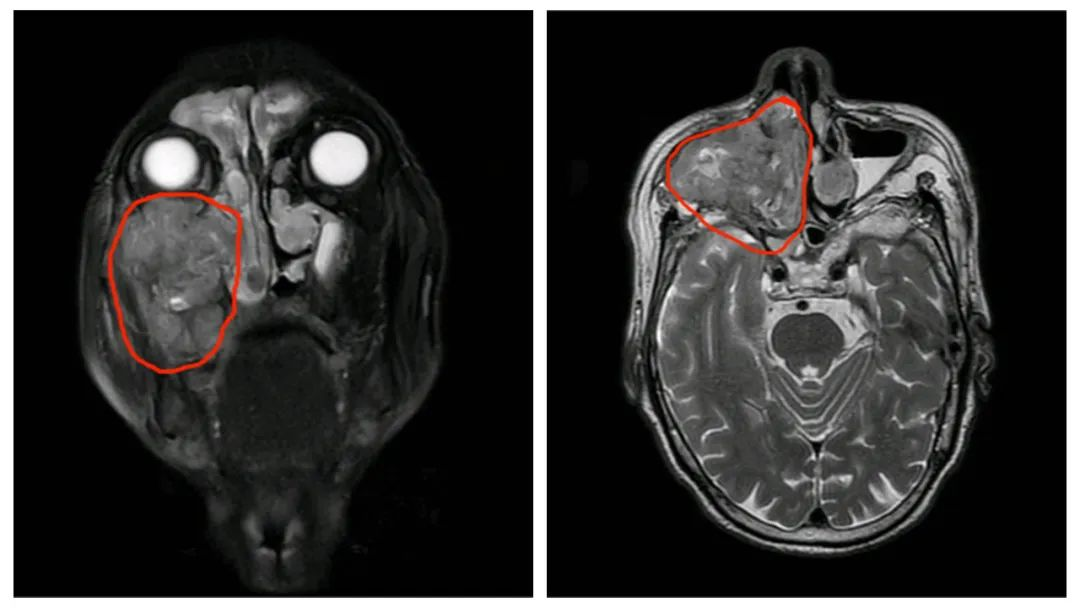

入住我院耳鼻咽喉头颈外科后,进行了一系列的检查,重点是病理活检及影像学检查,病理结果提示肿瘤性质为低分化鳞状细胞癌,而患者的影像学检查提示肿瘤侵犯范围大,突破了鼻腔鼻窦,累及了前颅底,翼腭窝、颞下窝,突破右侧眼眶底,向后侵犯鼻咽部侧壁。这意味着如果要用传统的手术方式切除肿瘤,必须行上颌骨全切,势必要牺牲患者的视力、正常的鼻腔功能及咀嚼、进食能力,并且会导致难看的颜面部畸形,术后生存质量极差。

术前MRI(所圈范围内为肿瘤病灶)